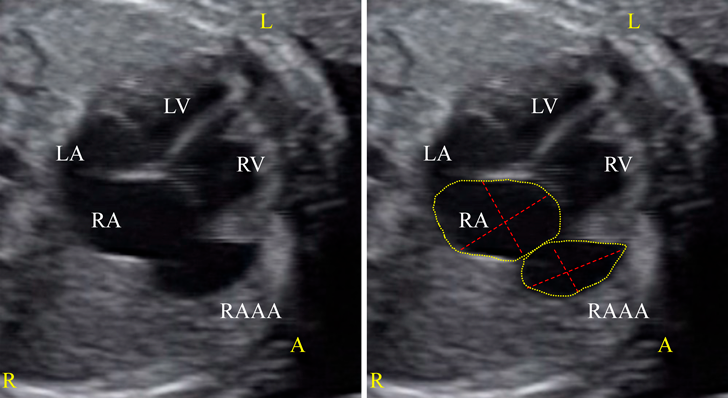

胎児期に診断し,無治療で経過観察できている先天性右心耳瘤の一例A Case of Congenital Right Atrial Appendage Aneurysm Diagnosed Prenatally and Followed-Up Without Treatment